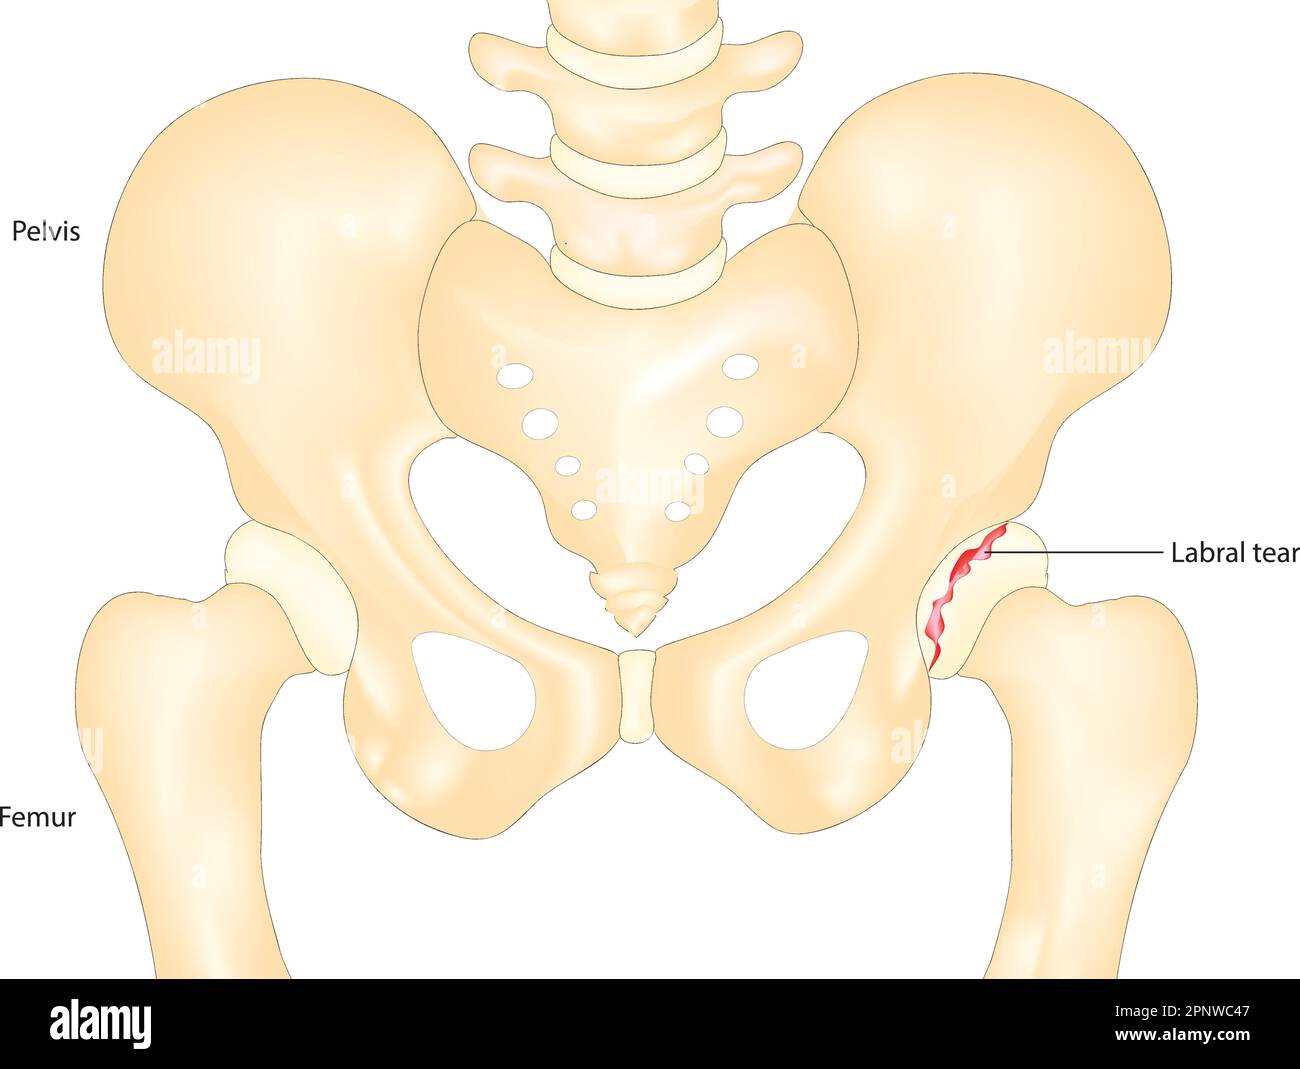

hip labral tear Stock Vectorhttps://www.alamy.com/image-license-details/?v=1https://www.alamy.com/hip-labral-tear-image546987511.html

hip labral tear Stock Vectorhttps://www.alamy.com/image-license-details/?v=1https://www.alamy.com/hip-labral-tear-image546987511.htmlRF2PNWC47–hip labral tear